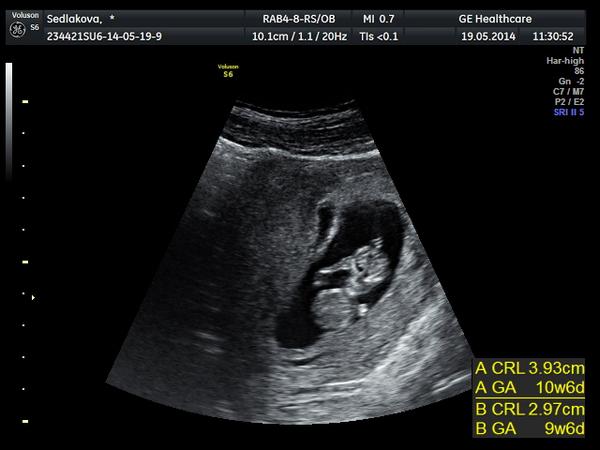

@elisc dekuji moc. No uz to zpracovávám a smiruju se s tom ze jsou opravdu dvě :D no po 4 letech "bušení "hihi aby vznikly je to fakt zazrak,kdyz jsem si rikala,ze mit deti nebudu a s tou myšlenkou uz žila a najednou k nam.prisli 2:D holky to je halusss,ja si furt pripadam ze spim a snim :D

@ivekr - krásný miminko, jak se tam rozvalujou, takže v práci končíš na dobro a budeš na neschopence, nebo se tam hodláš ještě vrátit? a jak je ti brouku, co blinkání už to ustává nebo ještě pořád? pěkně odpočívej, serfuj na internetu a vybírej pro mimísky a louskej dvojčecí diskuze, tam se dozvíš spoustu zajímavých věcí, ostatně jako tady mezi námi děvčaty 🙂